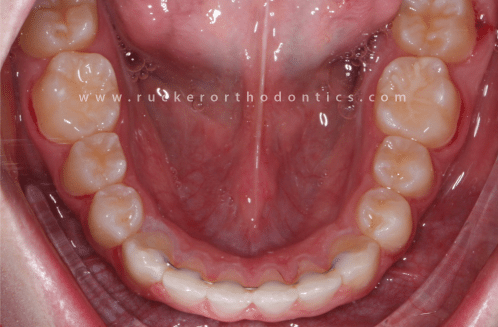

A bonded retainer, also known as a permanent retainer, is a type of metal retainer wire that is glued to the back of your teeth. They are typically placed on the lower teeth from canine to canine, but are also placed behind the upper teeth in certain situations. Although they are not permanently glued to your teeth, you will often them referred to as "permanent retainers." The reason for that is because bonded retainers are not removable by the patient. However, they can always be removed by a dental professional. With a little polishing of the glue that holds the wire in place the bonded retainer can be removed, leaving the tooth enamel in a healthy condition.